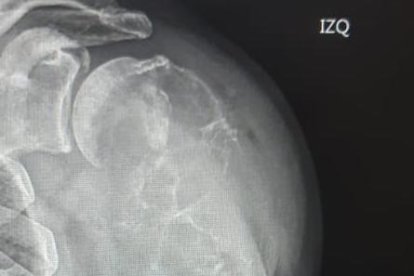

Su hombro izquierdo se dislocó mientras andaba en una bicicleta. No sufrió ningún accidente, solo bastó que hiciera una sencilla maniobra al pasar sobre un ‘vigilante acostado’, en una calle de la cooperativa Juan Montalvo, norte de Guayaquil, sector en el que reside hace tres décadas.

“Eso solo fue un pretexto. El brazo se me zafó del hombro por una bola que me apareció. La cabeza del húmero (hueso de la extremidad superior) ya no existe, el tumor se la ‘comió’ rápido”, cuenta.

El bulto mide aproximadamente ocho por quince centímetros, con proyección de crecimiento.